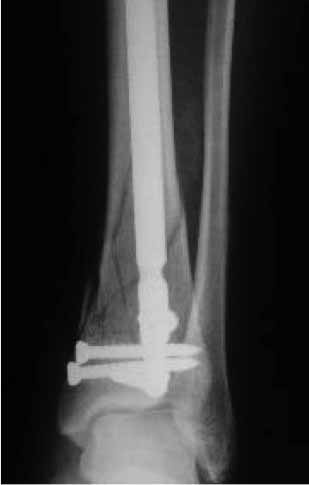

А после коррекции оси решить по окончательной фиксации. Вероятно, действительно можно будет заштифтовать. Рентгенологически сустав не потерян, так что действительно антеградно, как коллега Vlad предлагает. Имплантатов для короткого дистального отломка сейчас много. При штифтовании гвоздик должен быть сориентирован по фасу не на центр, а латеральнее, см. пример.